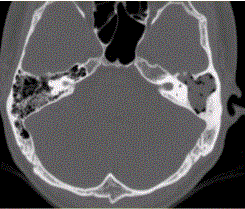

问题 患者男,25岁,右耳流脓液、听力下降5年。查体:右侧鼓膜穿孔,传导性耳聋,CT检查如下图。 慢性中耳乳突炎的并发症包括

选项 A.脑膜炎 B.脑脓肿 C.颅底骨髓炎 D.头皮下脓肿 E.颈内静脉炎和乙状窦脓肿 F.颈静脉球高位

答案 ABCDE

解析 ABCDE